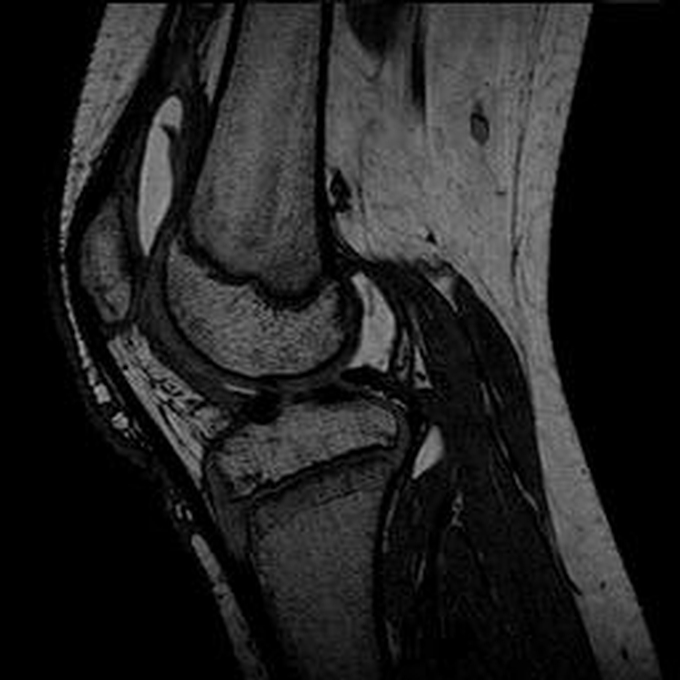

Haemophiliearthropathie bei Haemophilie A.

Arthropathia ARC123 Haemophiliearthropathie bei Haemophilie A.

MRT (high)